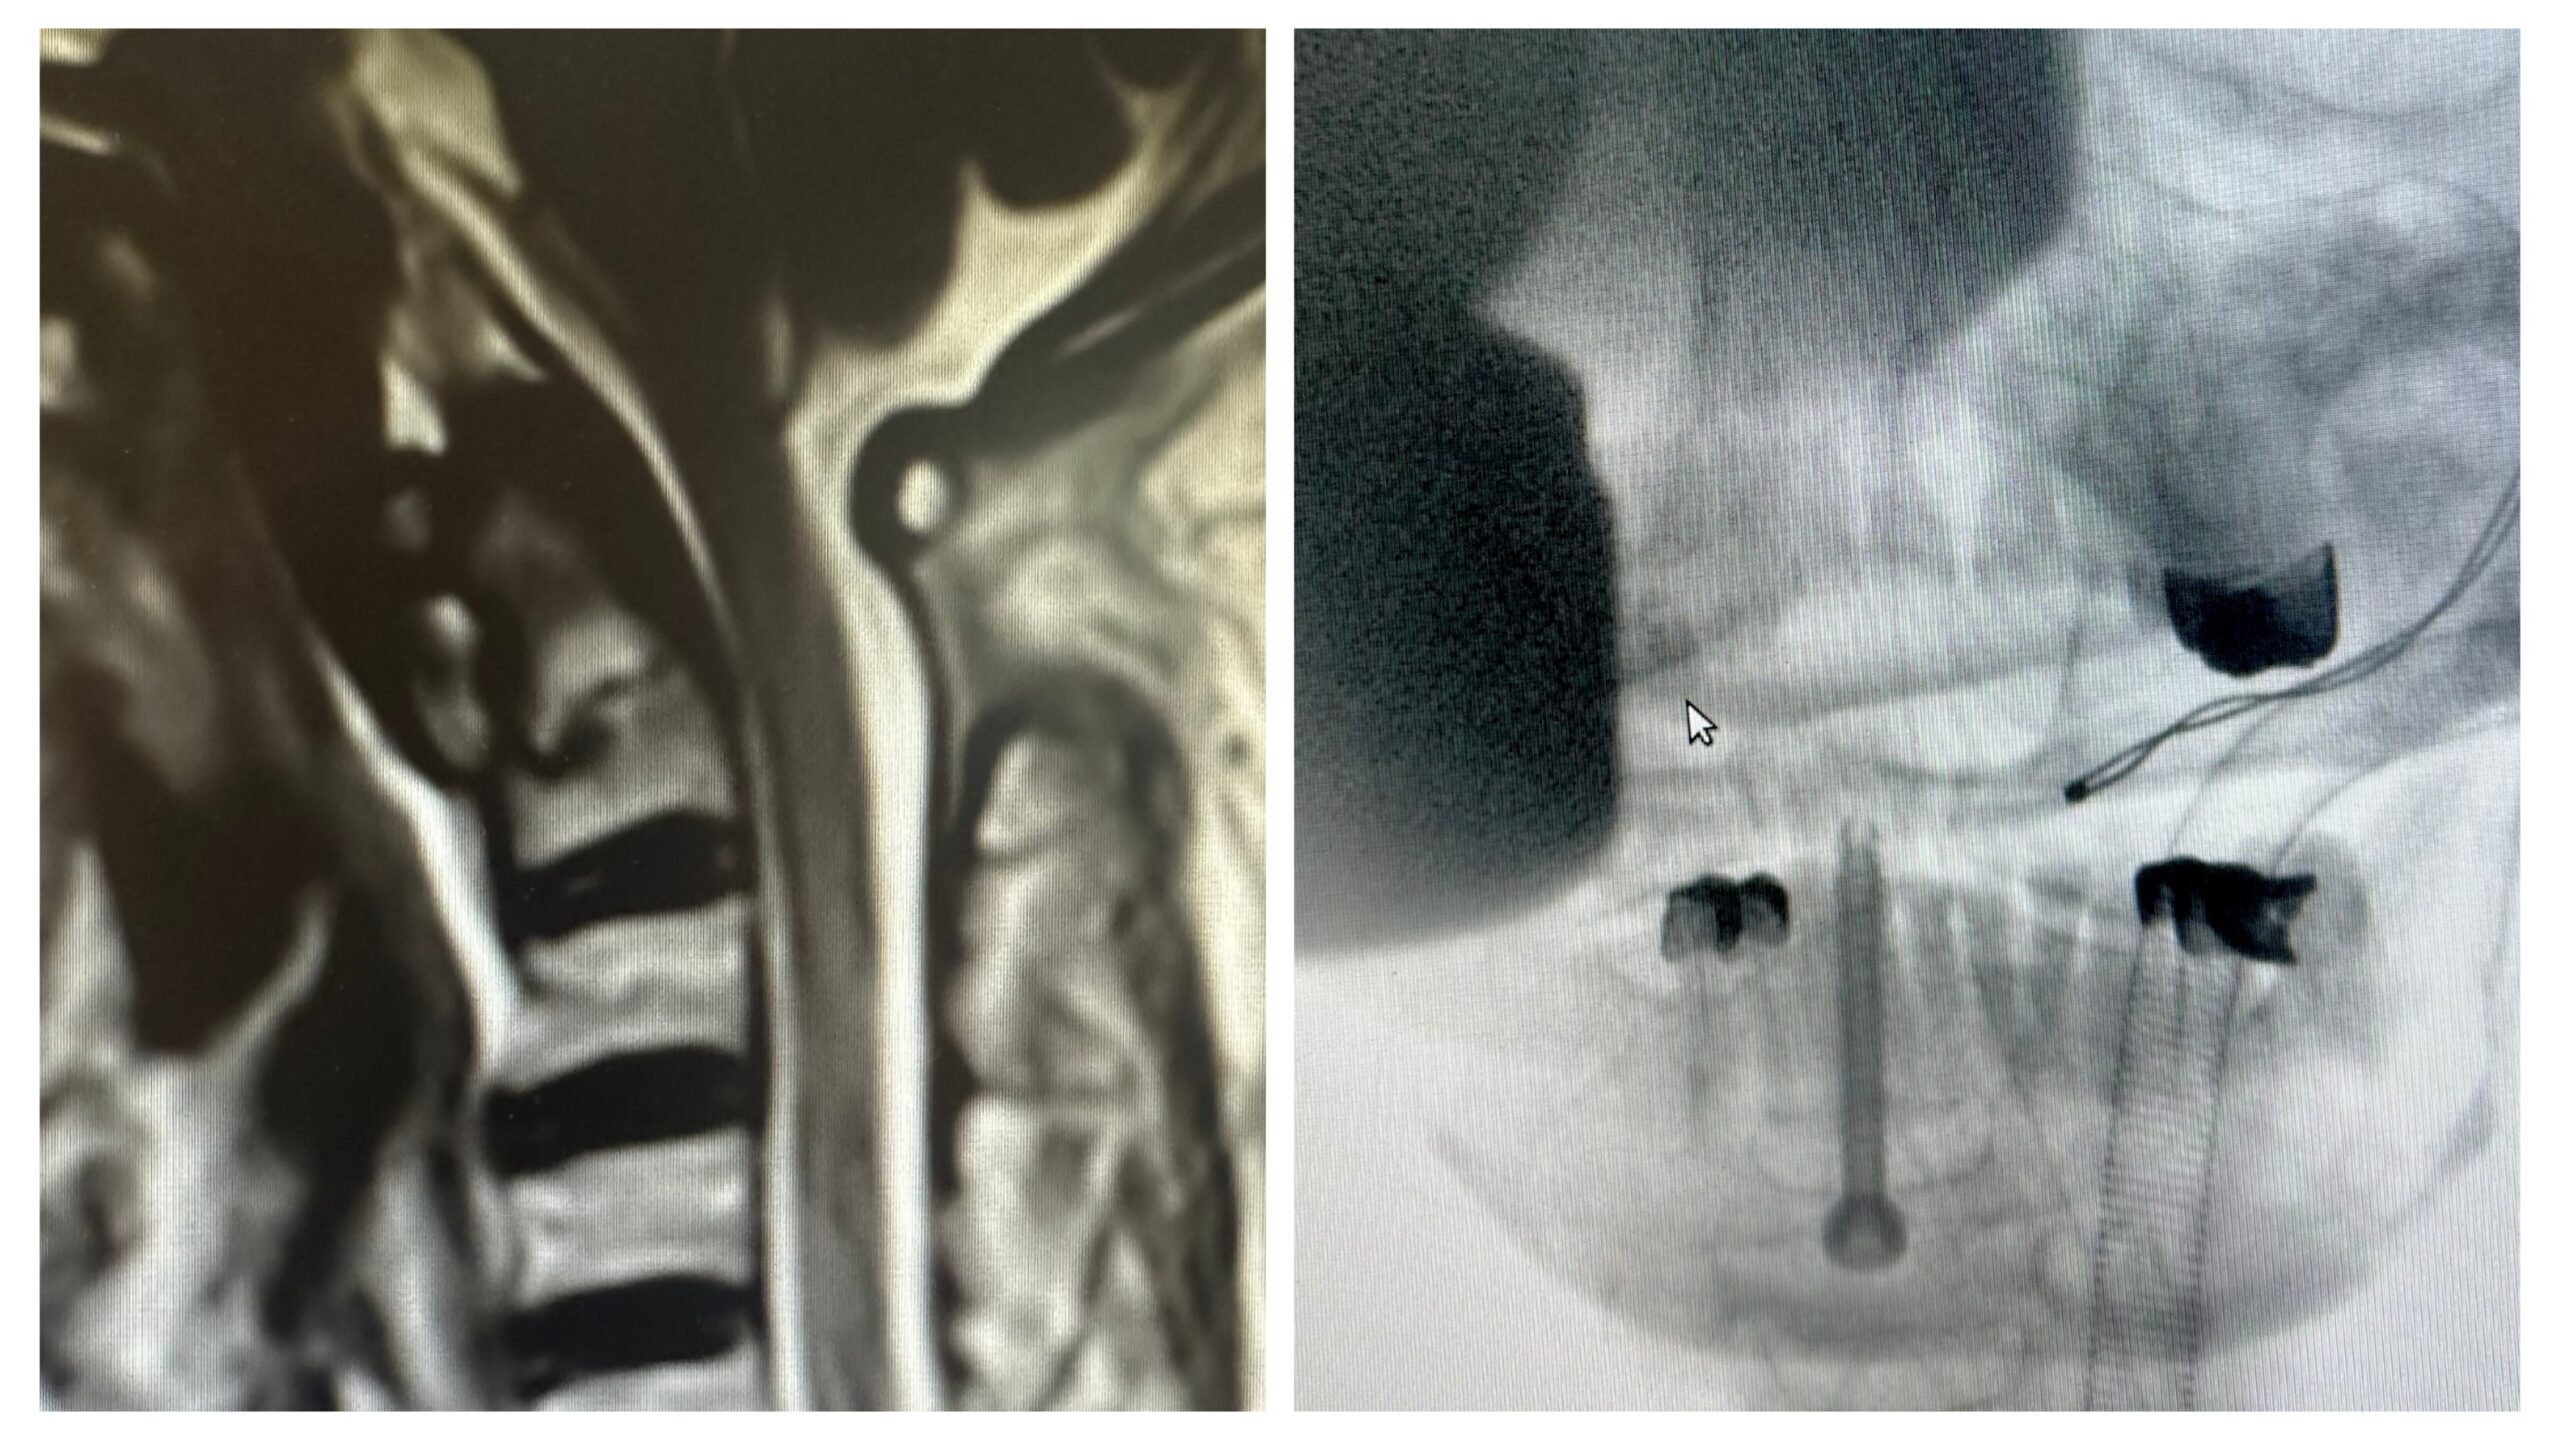

വീഴ്ചയിൽ കഴുത്തിലെ രണ്ടാമത്തെ കശേരുവിന്റെ ഭാഗമായ ഓഡണ്ടോയ്ഡിനു ഒടിവ് സംഭവിച്ച് ഗുരുതര നിലയിലായിരുന്നു. കഴുത്ത് നേരെ നിൽക്കാത്ത വിധത്തിലായിരുന്നു പരുക്ക്. ഓഡണ്ടോയ്ഡിനു ഒടിവ് സംഭവിച്ചാൽ തൊട്ടുപുറകിലുള്ള സുഷുന്മനാഡിക്കും, തലച്ചോറിന്റെ താഴെ ഭാഗമായ മെഡുല്ല ഒംബ്ലാംഗേറ്റയ്ക്കും ഗുരുതര ക്ഷതം സംഭവിക്കാൻ സാധ്യതയുണ്ടായിരുന്നു. മാർ സ്ലീവാ മെഡിസിറ്റിയിൽ എത്തിച്ച ശേഷം കന്യാസ്ത്രീയെ ആന്റീരീയർ ട്രാൻസ്ഓഡണ്ടോയ്ഡ് സ്ക്രൂ ഘടിപ്പിച്ച് കഴുത്ത് നേരെയാക്കുന്ന അപൂർവ്വ ശസ്ത്രക്രിയയ്ക്ക് വിധേയയാക്കി.

കഴുത്തിനു മുന്നിലൂടെ ചെയ്യുന്ന ഈ താക്കോൽദ്വാര ശസ്ത്രക്രിയയിലൂടെ ഒടിഞ്ഞിരുന്ന ഓഡണ്ടോയ്ഡിനെ കൂട്ടിയോജിപ്പിക്കാൻ സാധിച്ചു. ഈ ആധുനിക ശസ്ത്രക്രിയ രീതിയിലൂടെ കുറഞ്ഞ സമയത്തിനുള്ളിൽ ഗ്രാഫ്റ്റ് ആവശ്യമില്ലാതെ തന്നെ ശസ്ത്രക്രിയ പൂർത്തിയാക്കാൻ സാധിക്കുമെന്നതും പ്രത്യേകതയാണ്.